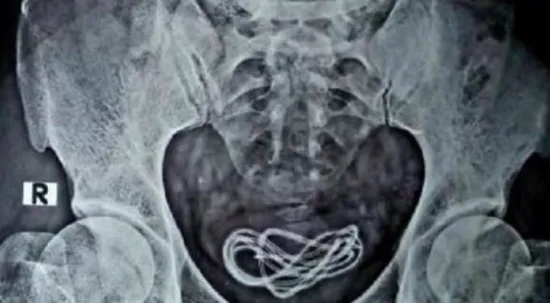

Hindistan'ın Assam eyaletinde tıp dünyasını şaşkına çeviren bir olay yaşandı. Olay, Hindistan'ın Assam eyaletindeki Guwahati kentinde meydana geldi. 30 yaşında olduğu belirtilen bir kişi, karın ağrısı şikayetiyle hastaneye gitti. Çekilen röntgende, kişinin mesanesinde yaklaşık bir metre uzunluğunda bir şarj kablosunun olduğu görüldü.

Hindistan medyası, karın ağrısı şikayetiyle hastaneye giden kişinin doktorlara, "Şarj kablosunu yuttum" dediğini duyurdu. Doktorlar ameliyat sırasında şarj kablosunun, kişinin cinsel organından mesanesine girdiğini tespit etti. Ameliyatı gerçekleştiren Dr. Walliul Islam, "Yaklaşık 25 yıldır cerrahım ancak şu ana kadar bir ameliyatta ilk kez böyle bir durumla karşılaştım" dedi.